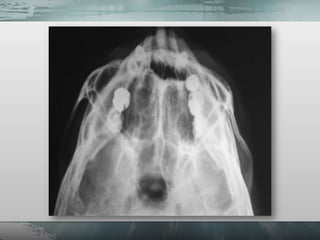

• 14.

• Planigrafias. – Incidência de Waters – Incidência de Hirtz (Axial). – Incidência para seios frontais (Caldwell). – Incidência para ossos próprios do nariz (perfil). • Tomografia computadorizada.